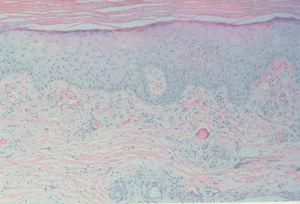

Fig. 5.--Trombo hialino en el vaso dérmico. (Hematoxilina-eosina, x250.)

En cuanto a los hallazgos histopatológicos la manifestación más frecuente es la vasculitis leucocitoclástica. También ha sido descrito un patrón de panarteritis necrosante de vasos del tejido celular subcutáneo similar a la panarteritis nudosa 13. La presencia de un material amorfo eosinófilo intravascular sin datos de vasculitis es más frecuente en la crioglobulinemia tipo I 11, sin embargo este hallazgo no es específico de este tipo como demuestra el caso de nuestras pacientes n.º 1 y 2 que presentaban este dato histológico asociado a una crioglobulinemia tipo II.